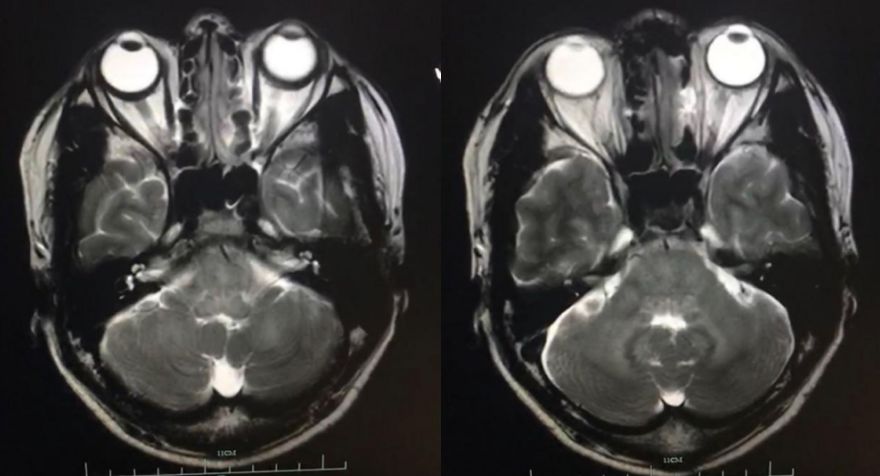

患者3月前发热后出现行走不稳,走路摇晃,伴口齿不利,偶有饮水呛咳,间歇发热,具体体温不详。 2月前症状逐渐加重,至外院就诊,头颅增强MRI:延髓、桥脑、中脑和桥小脑臂异常信号。诊断为“颅内多发病灶(脑干、小脑),代谢、炎症首先考虑,肿瘤不排除”(图1),入院后脑脊液检查:蛋白72.7mg/dL,有核细胞10/ul,墨汁染色及抗酸杆菌染色阴性。予呋喃硫铵、弥可保营养神经治疗,症状稍好转后出院,但仍间断发热。近1月来病情复发加重,来浙医二院就诊,头部增强磁共振显示脑干多发强化灶(图2)。为明确病因来浙医二院行立体定向活检术。门诊以“颅内多发病灶,性质待查”收住院。

图1. 外院MRI检查,提示颅内多发病灶(脑干、小脑),代谢、炎症首先考虑,肿瘤不排除。